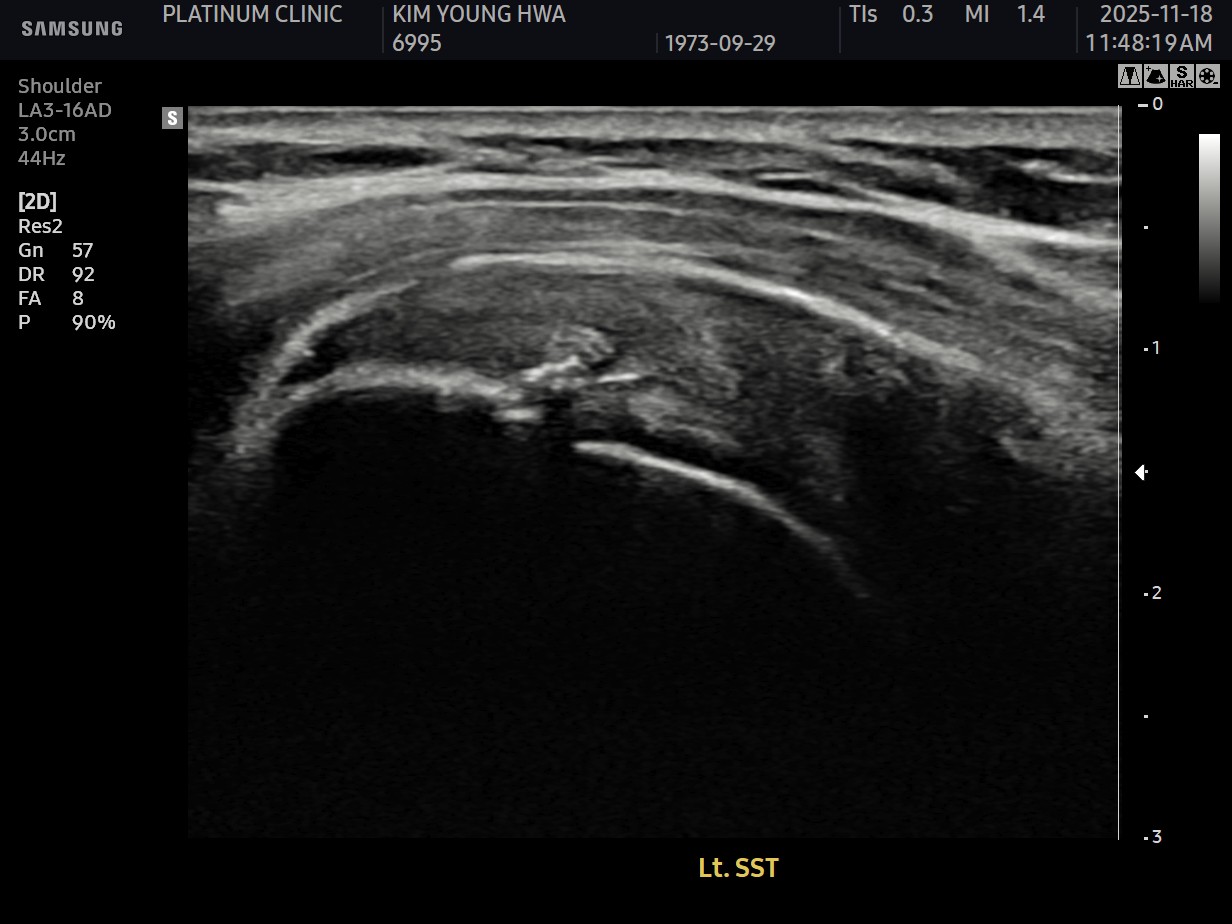

MRI와 초음파 검사 결과:

진단 결과:

- ✓관절면측 부분파열: 약 50%

- ✓점액낭면측 부분파열: 약 35%, 인대 얇아짐 동반

- ✓25년간 반복 사용으로 인한 퇴행성 변화 동반

양쪽 모두 손상된 복합 파열이었습니다.

- ✓관절면측: 봉합 부위 안정적 유지

- ✓점액낭면측: 인대 두께 4.8mm → 6.5mm (1.7mm 증가)